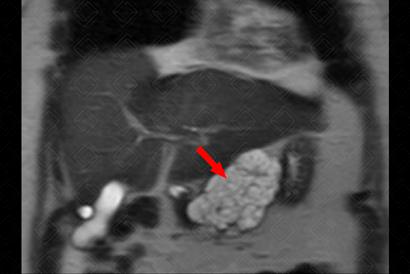

Texto alternativo para a imagem Figura 1. Créditos: Dra. Elazir Mota - Rio de Janeiro/RJ

Descrição da figura 1: Plano coronal, sequência T2, obtida em paciente do sexo feminino, 66 anos, evidenciando lesão lobulada, de aspecto microcístico, na cabeça pancreática (seta vermelha).